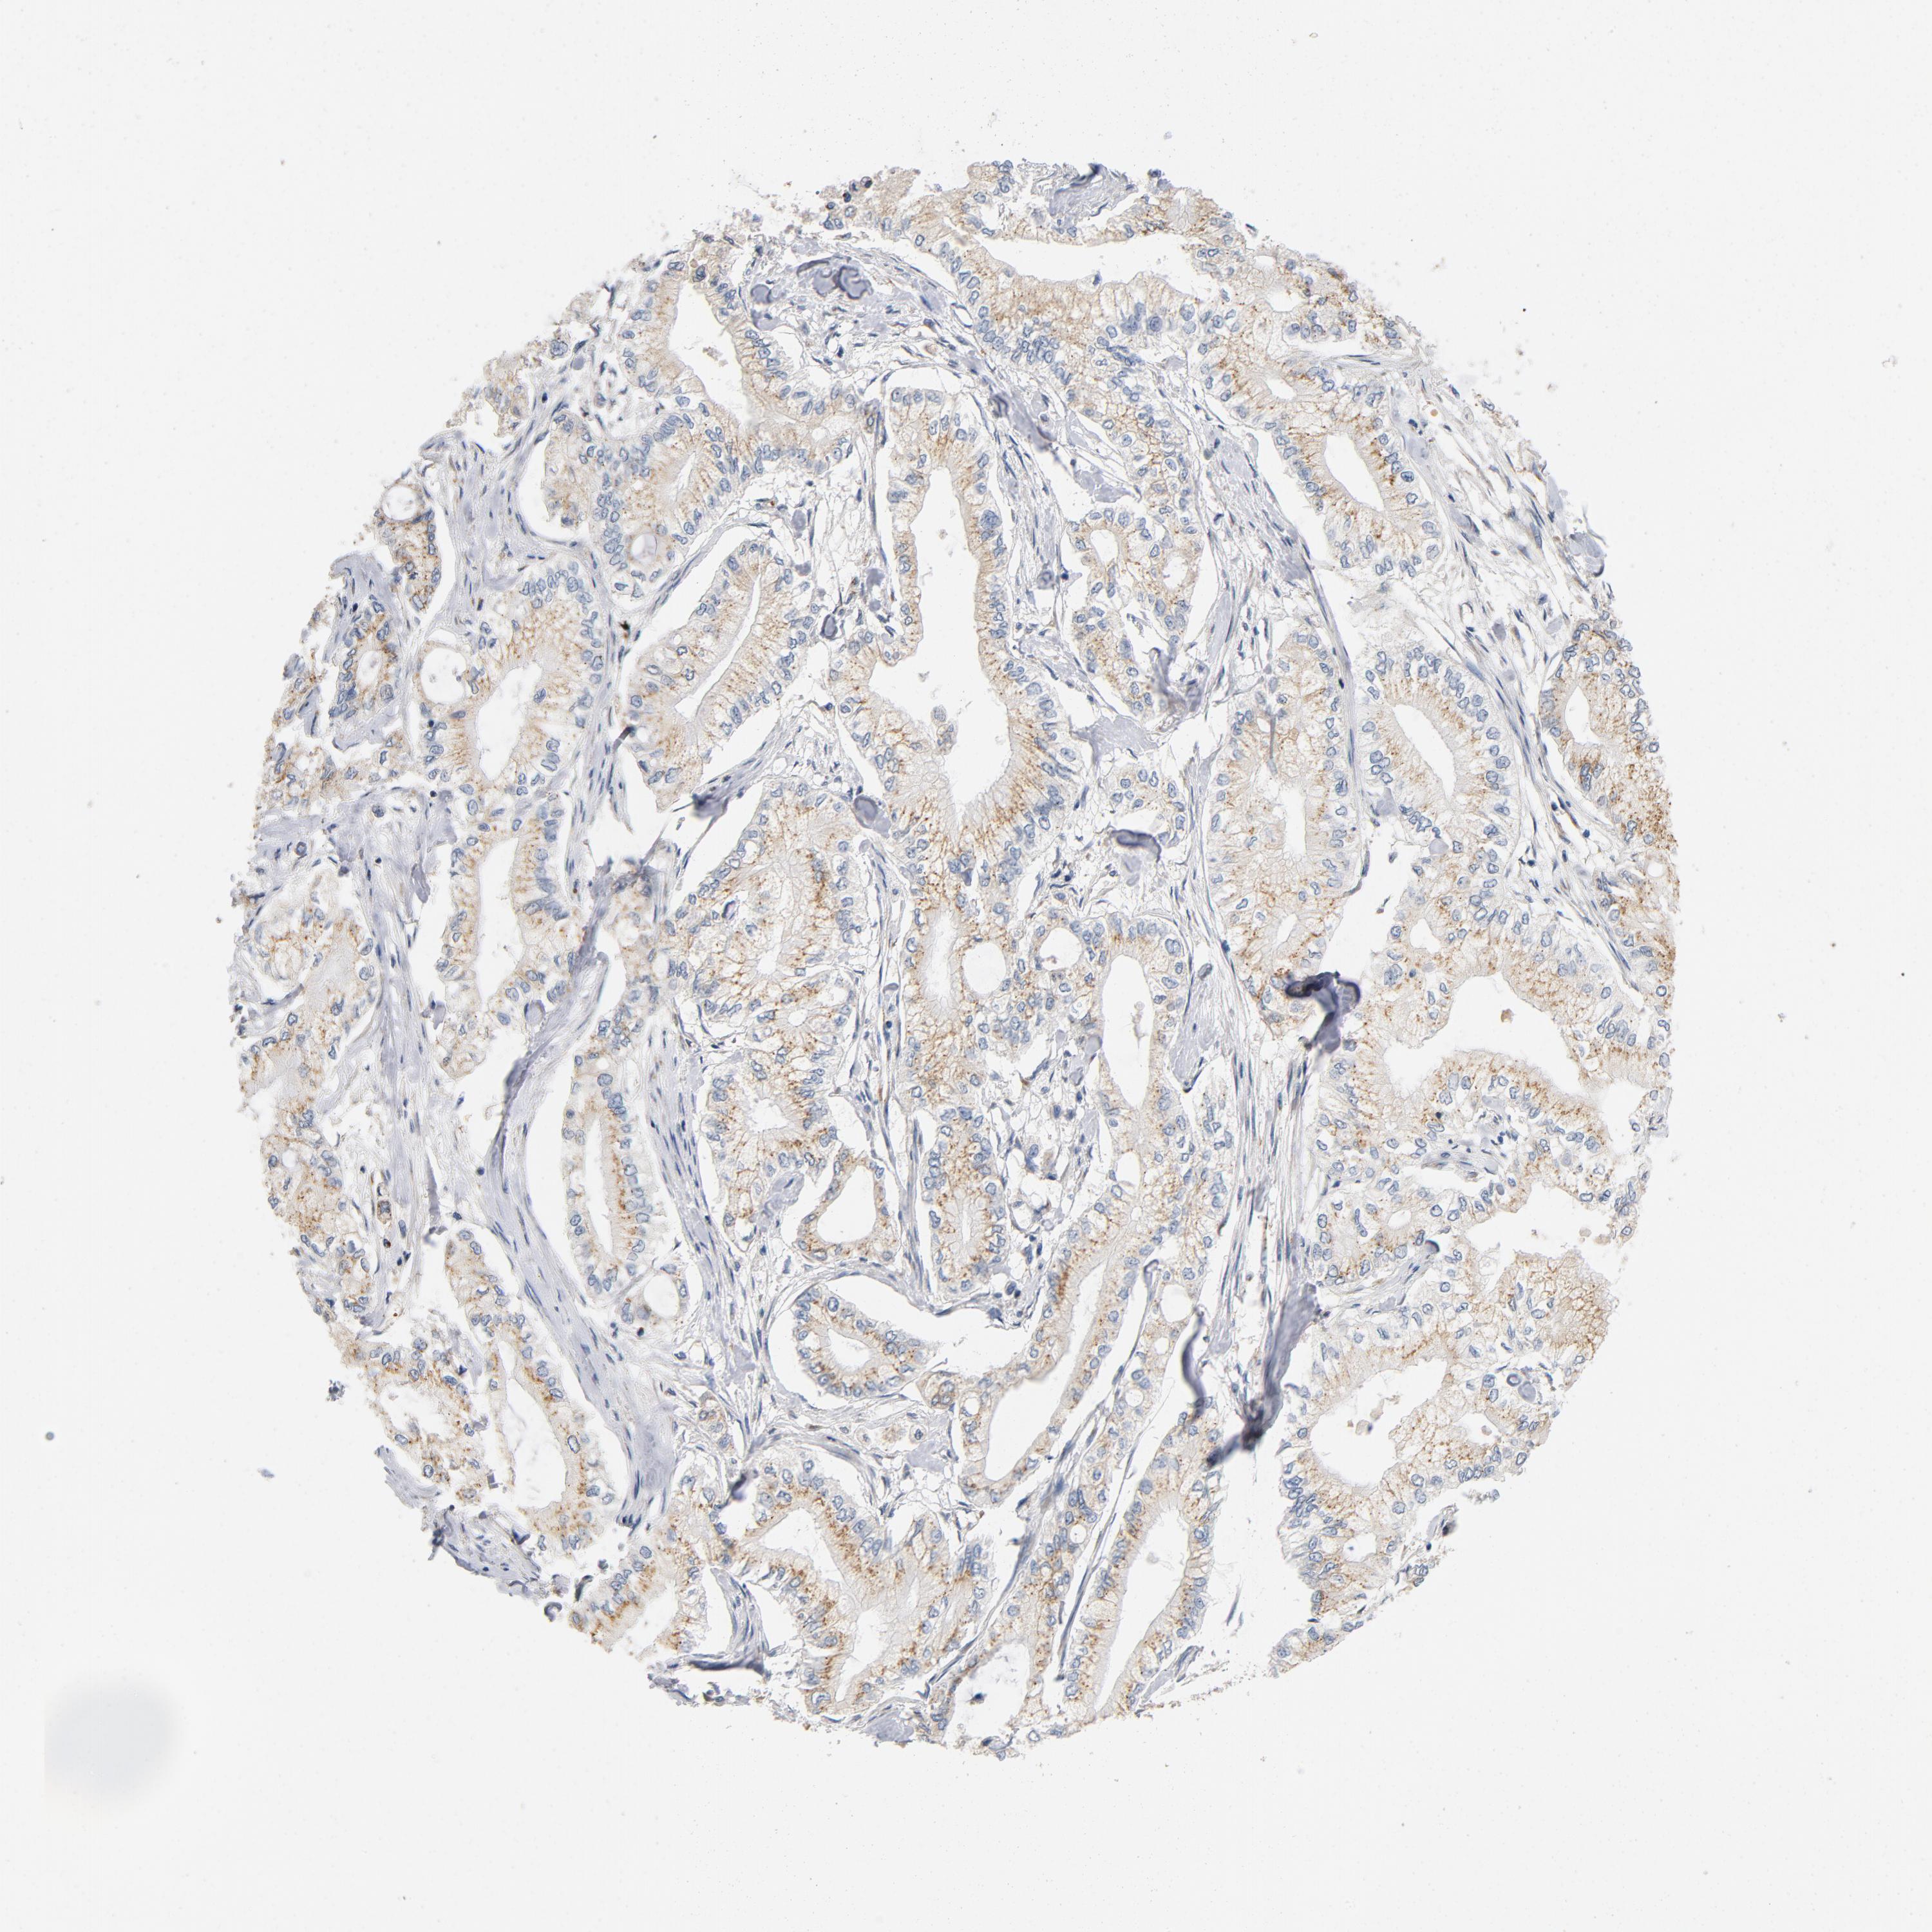

PANCREATIC CANCER - Protein expressioni

A mouse-over function shows sample information and annotation data. Click on an image to view it in a full screen mode. Samples can be filtered based on level of antibody staining by selecting one or several of the following categories: high, medium, low and not detected. The assay and annotation is described here.

Note that samples used for immunohistochemistry by the Human Protein Atlas do not correspond to samples in the TCGA dataset.

Antibody stainingi

Antibody staining in the annotated cell types in the current human tissue is reported as not detected, low, medium, or high, based on conventional immunohistochemistry profiling in selected tissues. This score is based on the combination of the staining intensity and fraction of stained cells.

Each image is clickable and will lead to virtual microscopy that enables deeper exploration of all samples and also displays staining intensity scores, fraction scores and subcellular localization as well as patient and tissue information for each sample.

Antibody HPA003927

Staining

High

Medium

Low

Not detected

Intensity

Strong

Moderate

Weak

Negative

Quantity

>75%

75%-25%

<25%

None

Location

Nuclear

Cytoplasmic/membranous

Cytoplasmic/membranous,nuclear

Adenocarcinoma, NOS